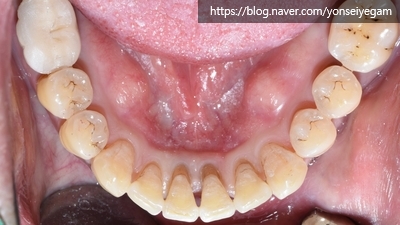

[2020년 3월]

6개월만에 교정장치가 보이지 않는 비밀스런 설측교정으로

요렇게 완료되고 유지장치까지 완성되었습니다.